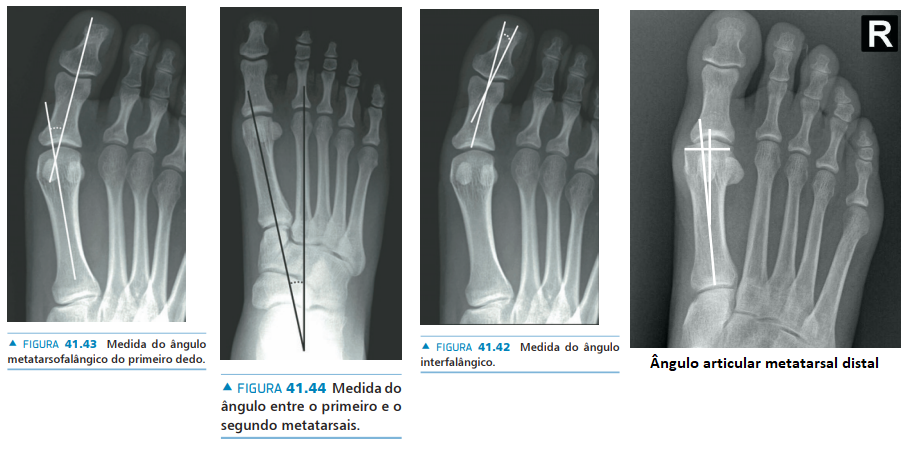

• Na avaliação radiográfica em AP com carga, quais os principais ângulos a serem traçados?

A

• Ângulo de valgismo do hálux (metatarsofalângico)

• Ângulo intermetatarsal

• Ângulo de valgismo interfalângico do hálux

• Ângulo articular metatarsal distal (AAMD)

• Na radiografia em AP com carga, como é traçado o ângulo intermetatarsal?

• Ângulo entre o eixo longo do 1° e do 2° raio

• Normal → até 9°

• Leve → 9° a 12°

• Moderado → 13° a 15°

• Grave → > 16°

17

Q

Hálux valgo

• Na radiografia em AP com carga, como é traçado o ângulo de valgismo do hálux (metatarsofalângico)?

• Ângulo entre o eixo longo do 1° mtt e o eixo longo da falange proximal

• Normal → até 15°

• Leve → < 25°

• Moderado → 25° a 40°

• Grave → > 40°

18

• Na radiografia em AP com carga, como é traçado o ângulo de valgismo interfalângico do hálux?

• Ângulo entre o eixo longo da falange proximal e o eixo longo da falange distal

• Normal → até 10°

19

• Na radiografia em AP com carga, como é traçado o ângulo articular metatarsal distal (AAMD)?

• Traça-se uma linha unindo os dois pontos mais largos da superfície articular do 1° mtt e outra linha perpendicular a esta

• Depois, traça-se uma linha no eixo longo do 1° mtt

• O ângulo entre as duas maiores retas → até 15°